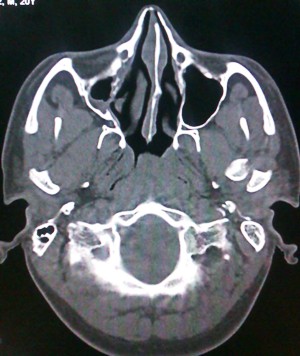

Case 1: A 40-year-old female patient reported to the department of dentistry, with the chief complaint of pain during mastication in the left preauricular region. There was a history of fall from bike one week before. There was no pain or swelling present initially, but she developed pain after one week of trauma which subsided by medication. No history of ear bleed was reported. On palpation, head of the condyle was present in the glenoid fossa, with diminished movements on the left side. In the OPG no fracture was visible. The initial diagnosis of traumatic arthritis was made, and the patient has advised a soft diet and moist heat application. Though the intensity of pain reduced after 2 weeks,it persisted,hence theC.T scan was advised. Computed tomography revealed bony changes in the fractured mandibular condyle and its position in the mandibular fossa more precisely than conventional radiographic examinations. In the axial section, there was a sagittal fracture of the left condyle. Intermaxillary fixation was done for two weeks.

Figure 1. Axial CT showing vertical fracture of left condyle of mandible.